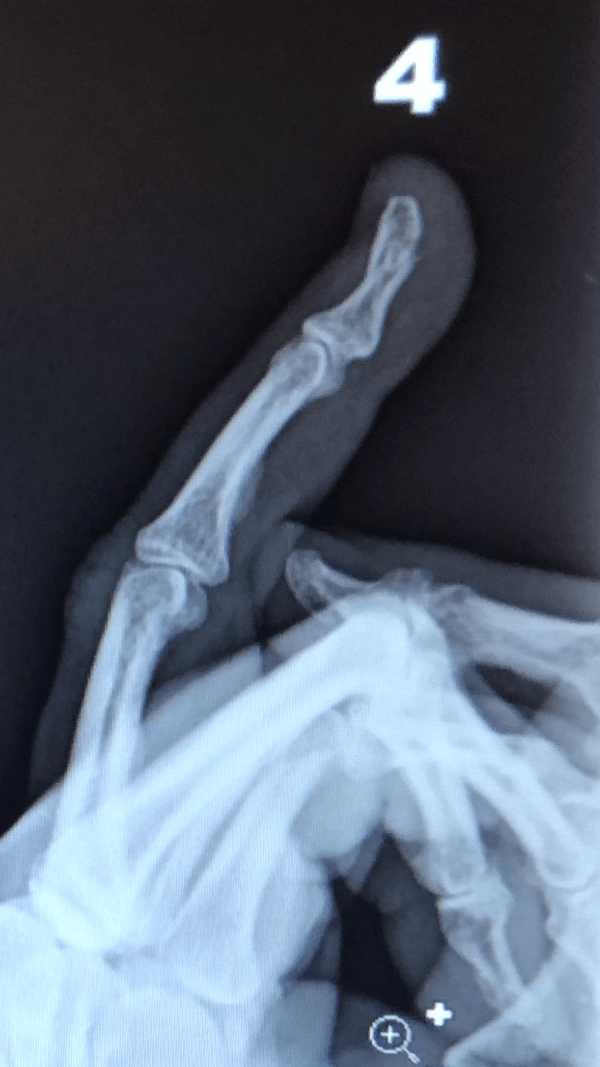

They took X-rays and sure enough, the end of my fourth finger showed a break even I could see on the X-ray. They put a splint on it and sent me home with instructions to see an orthopedic surgeon and I may take Tylenol for the pain.

My understanding is that the end of fingers is made of softer bone and it breaks more easily. It also gets limited blood flow and there is not too much they can do for it.